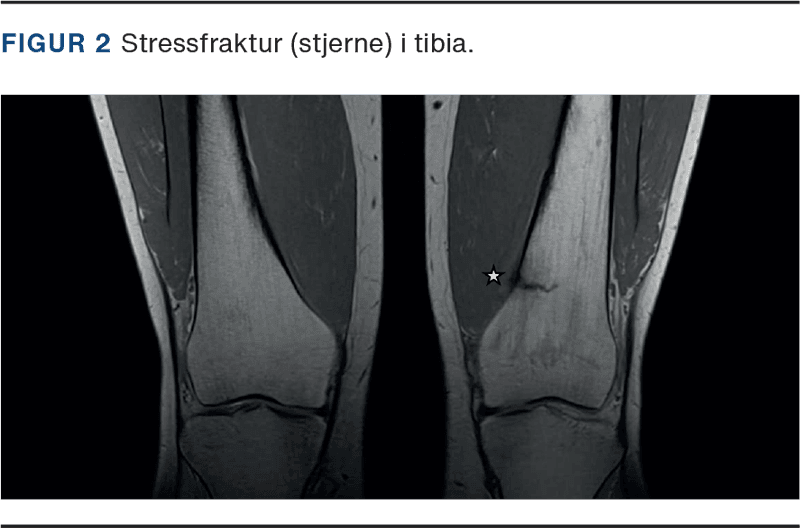

MR-skanning

MR-skanning er guldstandard til diagnosticering af SF med sensitivitet og specificitet beskrevet på hhv. 88% og 100% [16]. Derudover kan MR-skanning detektere knoglemarvsødem uger før, at der kan ses radiologiske forandringer [17] (Figur 2).